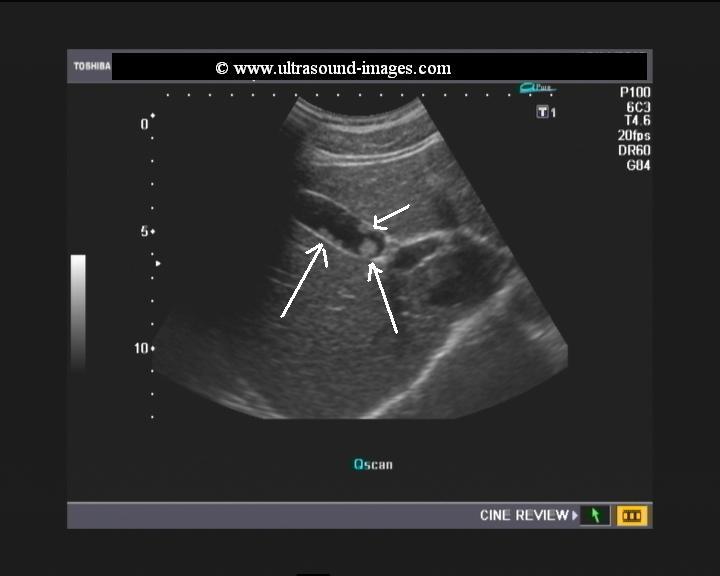

Ultrasound images of lesions of gall bladder wall

This patient underwent routine sonography of the abdomen. Ultrasound images of the gall bladder reveal thickening and constriction of the mid segment dividing the lumen into a fundic area and another part towards the neck. There is also evidence of small calculi in the fundic segment of the gall bladder. These ultrasound images suggest segmental adenomyomatosis of the gall bladder. Adenomyomatosis of the gall bladder may be segmental, diffuse or fundal. Images taken using Toshiba Powervision ultrasound and color doppler machine, courtesy of Dr. Ravi Kadasne, Al Ein, UAE.